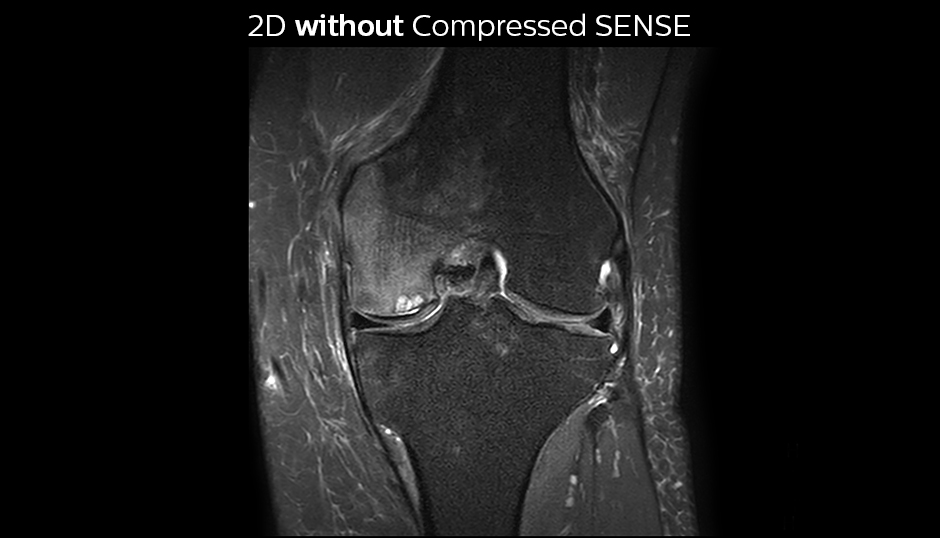

Comparing 2D with 3D using Compressed SENSE

A good acquisition time with high resolution is obtained when moving from three 2D acquisitions in three planes to one 3D acquisition with Compressed SENSE. In this example, Compressed SENSE with 3D VIEW PD SPAIR is 50% faster than three separate 2D scans and has improved spatial resolution.

Without Compressed SENSE Scan time 2:55 + 3:37 + 3:51 = 10:23 min. Voxel size 0.55 x 0.65 x 3 mm

Three separate 2D PD scans in three orientations

With Compressed SENSE factor 10 Scan time 5:03 min. Voxel size 0.6 x 0.6 x 0.6 mm

3D VIEW PD SPAIR high resolution knee